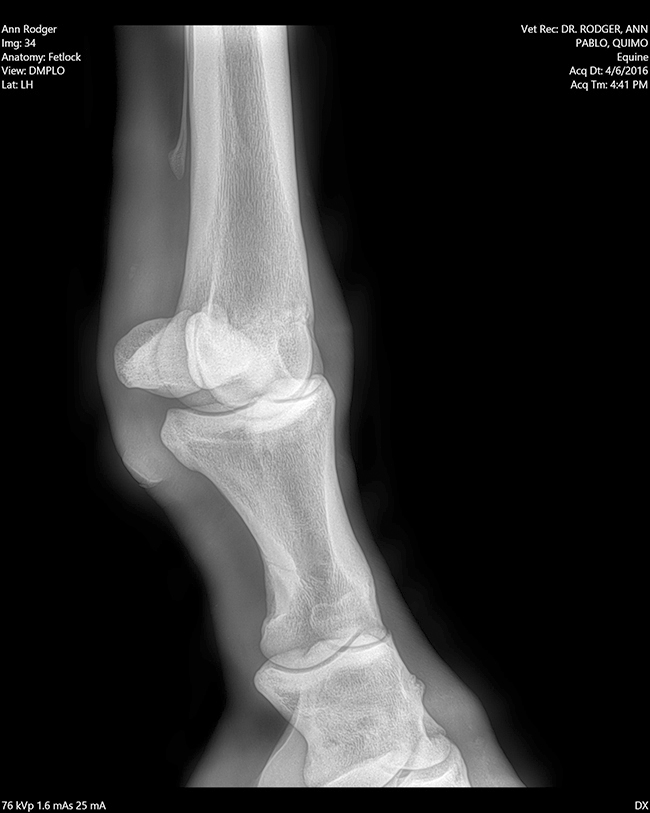

Radiología

Contamos con el equipo de radiología digital inalámbrico más avanzado del país, el cual permite obtener las mejores imágenes en el acto y compartirlas vía mail. Realiza radiografías de miembros, columna, cabeza, cuello y hombro.